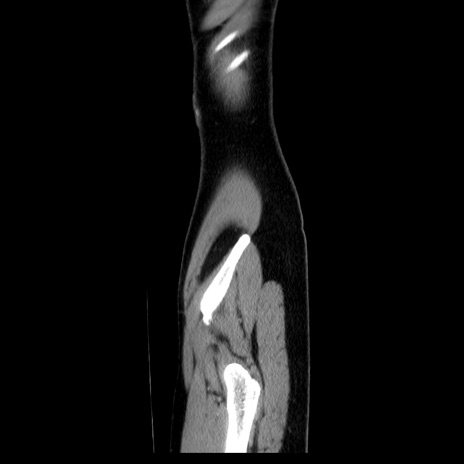

症例39(矢状断像)

【症例】40歳代女性

【主訴】上下腹部痛

【現病歴】2日目から下腹部痛あり。夜間は痛みで眠れなかった。昨日より上腹部痛と下痢が出現。臥位で痛みは軽快したため、休んでいた。本日になって臥位でも立位でも痛みが強くなってきたため救急要請。

【既往歴】子宮内膜症

【身体所見】部:平坦・軟、左上下腹部に圧痛あり、反跳痛あり。

【データ】WBC 21800、CRP 26.78

CT